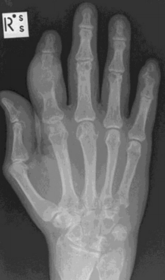

| What disease is this? | Rheumatoid arthritis |

| What disease is this? What indicates this? | Tophaceous gout. Soft tissue swelling surrounding the index finger PIPJ, with associated erosion and bone resorption |

| What disease is this? | Tophaceous gout. |